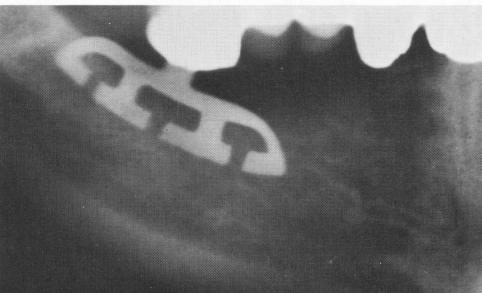

Fig. 11-40. Radiograph of completed case.

4 Radiograph showing unilateral mandibular restoration by blade implants